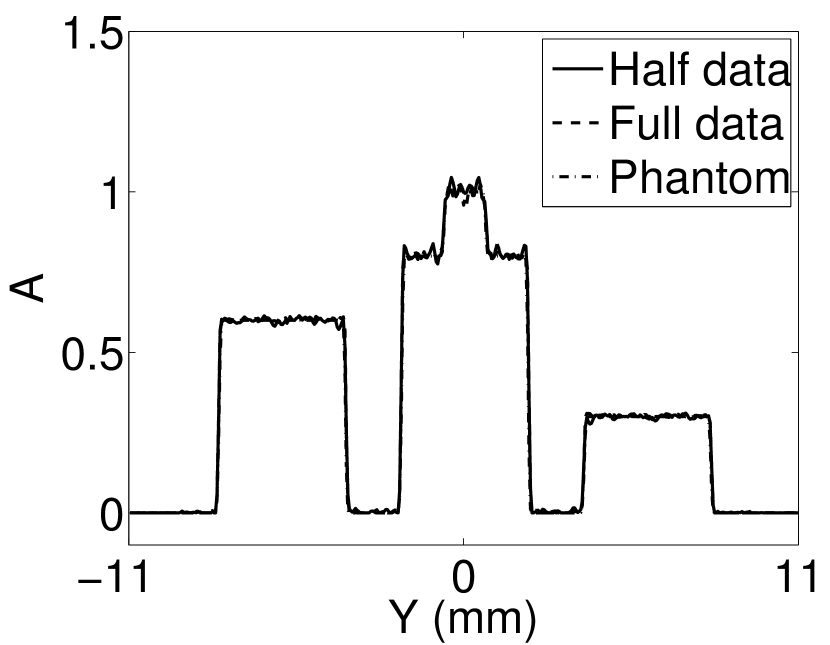

V-A3 Effect of data incompleteness

Incomplete, or sparsely sampled, data sets are sometimes acquired in practice. To study the effect of data incompleteness on the VP algorithm, we reconstructed images from data corresponding to half of the equally spaced transducers (). Because the data were noiseless, no explicit regularization was employed () in the conventional reconstruction algorithm. However, the explicit regularization was still employed in the VP algorithm because of the ill-posed nature of the joint reconstruction problem. The results are shown in Figure 5. As expected, use of the incomplete data set resulted in less accurate reconstructed images for both the conventional iterative reconstruction method and the VP algorithm. However, this effect was more pronounced for the VP algorithm. Note that for the VP algorithm, larger values of the regularization parameters were applied when the incomplete data set was employed than when the complete data set was employed (Figure 5(h) and 5(g)).